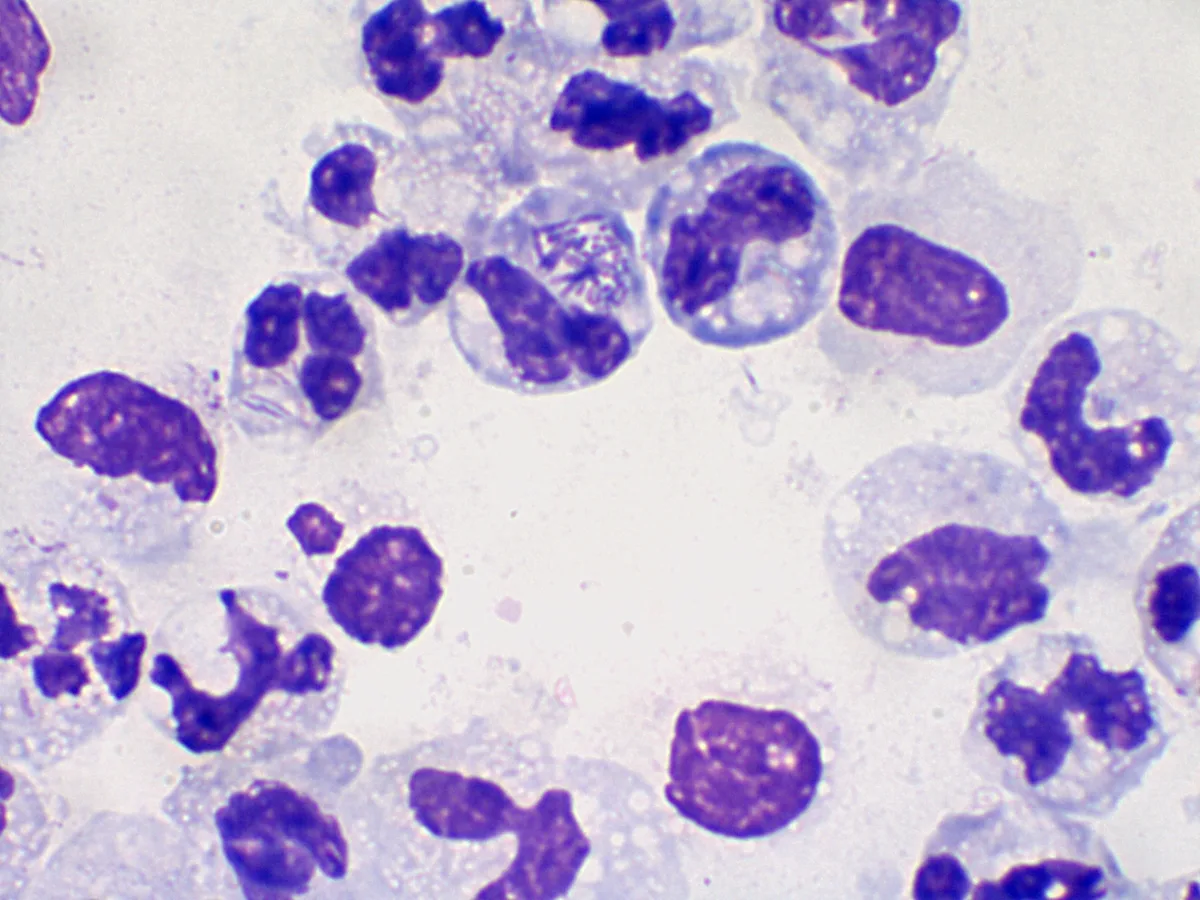

Clinical Image